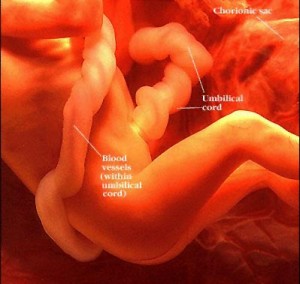

25 haftalık bebek Bebeğinizin boyu 30 cm oldu. İç kulağındaki kemiklerde sertleşmeye başladığından artık sizi daha iyi duyabiliyor. Aslında babasının sesini, sizin sesinizden daha net duyabiliyor. Eşinize söyleyin, karnınıza yaklaşıp bebeğinize “Merhaba” desin lütfen !